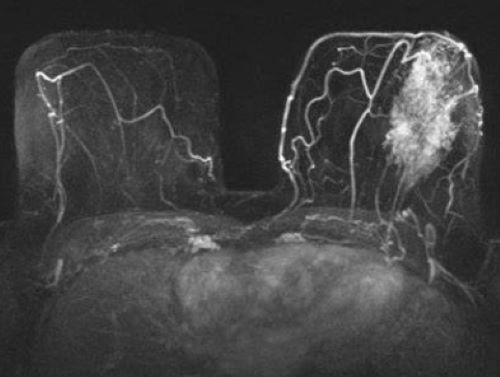

Mamma MRT mit Kontrastmittel

Bei einer Mamma MRT wird häufig ein Kontrastmittel verwendet, um die Untersuchung deutlich zu verbessern:

Das Kontrastmittel verbessert somit sowohl die Diagnosesicherheit als auch die Genauigkeit bei der Beurteilung des Tumors.